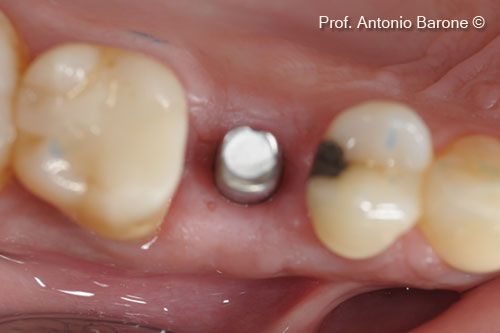

Hình ảnh lâm sàng của implant đã được cấy ghép. Đo độ dày xương mặt ngoài

Hình ảnh lâm sàn mặt nhai sau khi bộc lộ implant